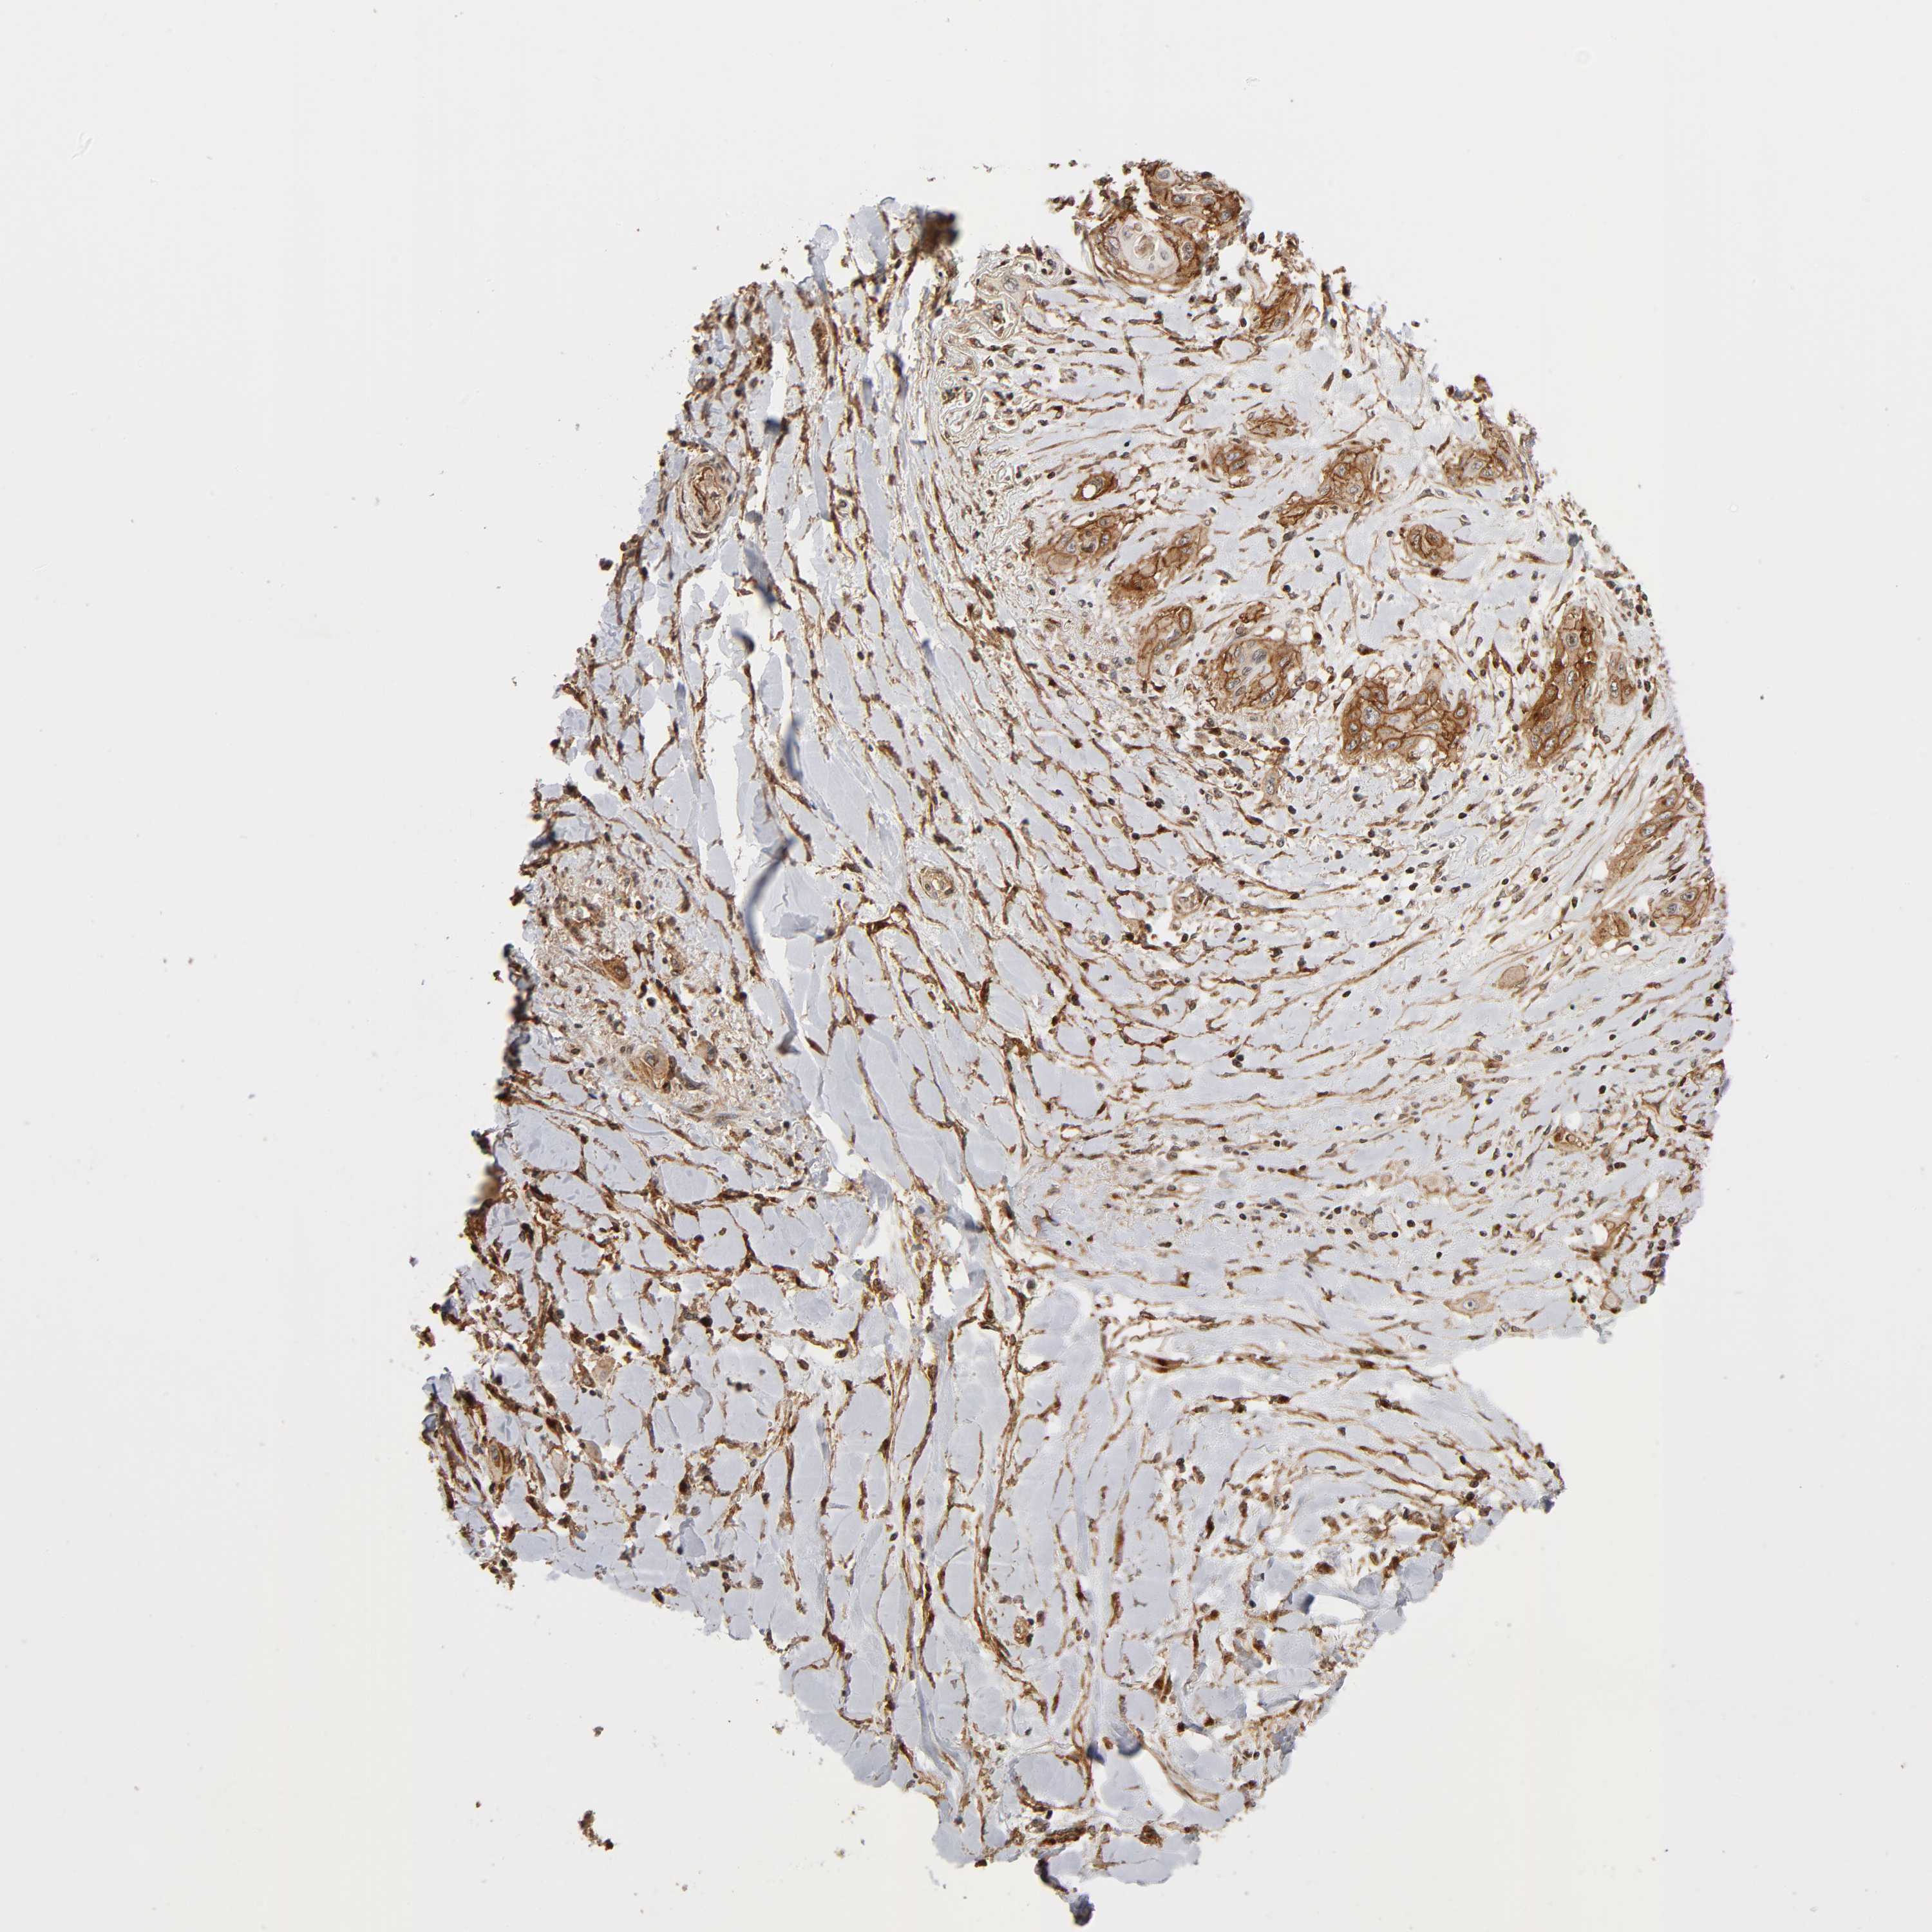

CANCER LUNG CANCER Show tissue menu

LUAD TCGA LUAD VALIDATION LUSC TCGA LUSC VALIDATION PROTEIN LUAD CPTAC PROTEIN LUSC CPTAC PROTEIN EXPRESSION

ANTIBODIES

AND

VALIDATION